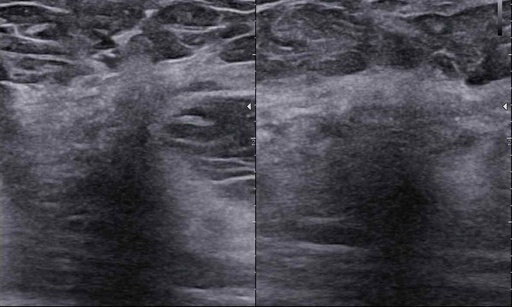

Nagranie webinaru: BI-RADS-usg case story

Czy my rzeczywiście potrafimy czytać tę skalę? Dlaczego tyle jest rozbieżności?

Czy podział BIRADS 4 ma sens? Jak radzić sobie  z BIRADS 4a, b, c?